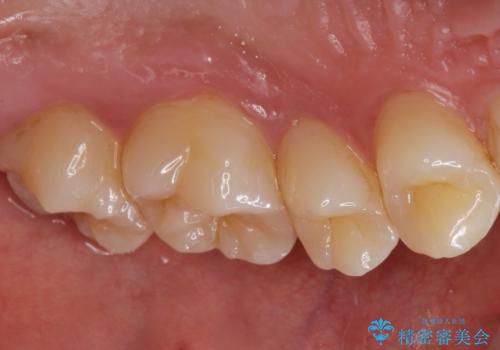

コンタクトカリエス治療。

- 歯と歯の間に虫歯(コンタクトカリエス)が見られたので拡大鏡下で取り除き、e-maxインレーで治療を行いました。